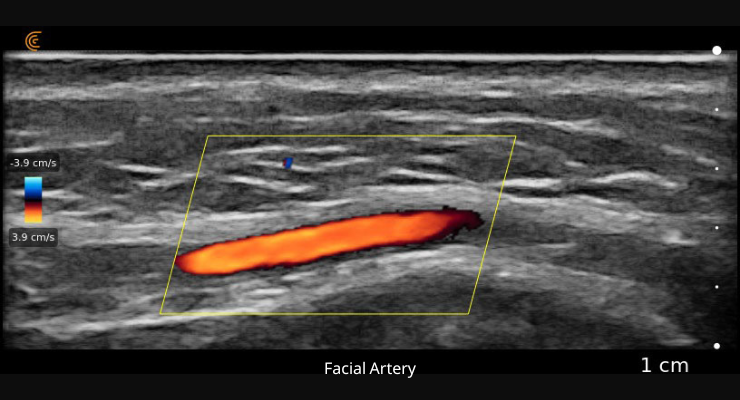

• הדמיה ברורה למיפוי של הרקמה ומניעה של חסימת כלי דם

•י כולת ברורה לראות את מיקום המחט או הקנולה לפני ההזרקה

• מאפשר טיפול בטוח להמסת חומר מילוי ו/או טיפול ואבחון סיבוכים אחרים